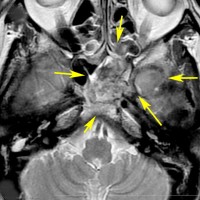

巨大なエコルドーシス・フィサリフォラ

骨をみているCTです。鞍背からsphenooccipital synchondrosisまでの斜台骨皮質が失われています。かなり特徴的な所見です。

T2強調画像とFLAIR像です。FLAIRでは髄液より高信号となります。のう胞様の膨らみを有します。脊索腫と異なり,expanding mass と表現されます。

CISSとガドリニウム増強T1強調画像です。ガドリニウム増強されません。